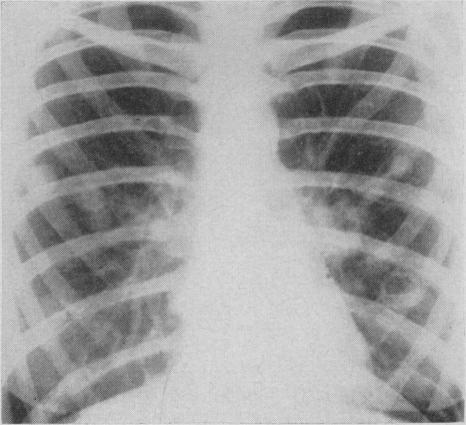

Pulmonary histoplasmosis.

Can Med Assoc J. 1959 Sep 15;81(6):486-8.